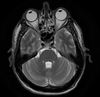

Když už máme tu okurkovou sezónu a řeší se tu všelicos, docela dost třeba právě zdravotní neduhy, které ke sportu samosebou patří, co najít mezi sebou toho největšího lazara a třeba i hypochondra? Máte jedinečnou možnost se pochlubit, co všechno vás bolí a kde máte jaký bebí. fotografická dokumentace vítána:-)